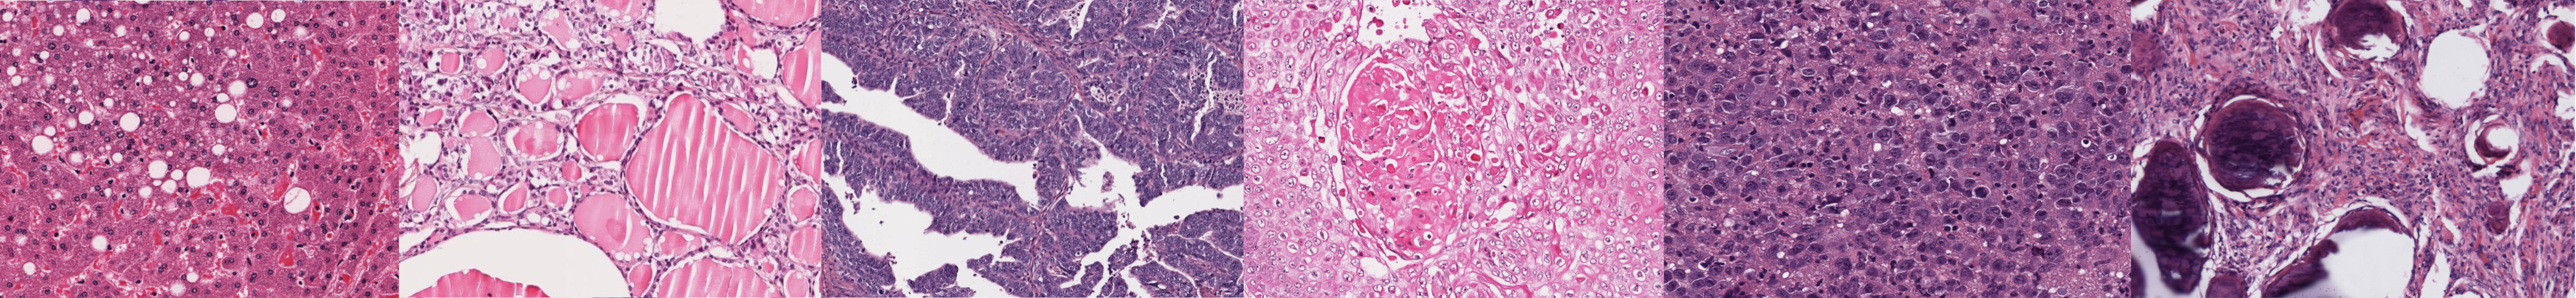

Museo microscópico de patología de la Universidad del Rosario

Tracto gastrointestinal

Dermatología

Tracto genital femenino

Tracto genital masculino

Patología infecciosa

Patología renal

CPC

Inflamación, acúmulos y envejecimiento

Neoplasia

Hematología

Patología mamaria

Sistema nervioso central

Corazón y vasos sanguineos

Huesos y articulación

Pulmón